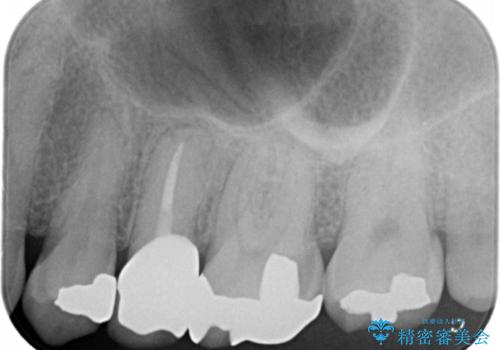

- 歯の根のあたりの歯ぐきを押すと痛むことを主訴に来院された患者様です。

精査したところ、左上の小臼歯(左上5)の神経が死んでいました。

根管治療後、セラミッククラウンによる補綴を行いました。